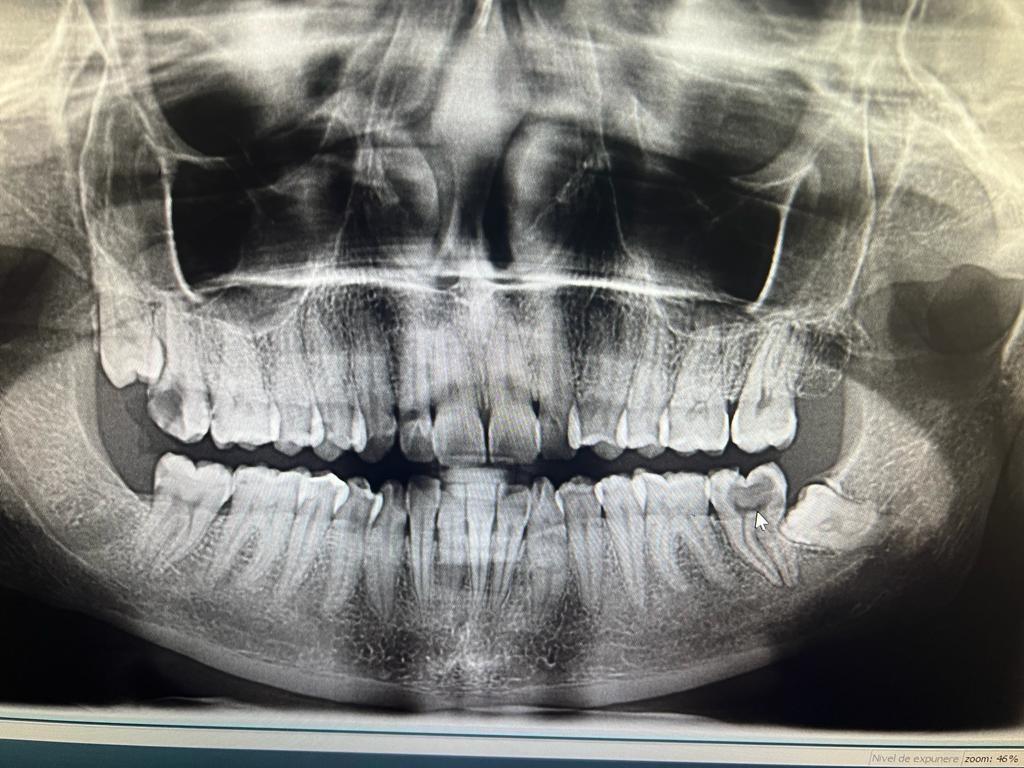

Clinica LUY ESTHETIC ART defineste parodontoza ca fiind rezultatul direct al placii dentare, care se depune pe suprafata dintilor, dar si in apropiere de marginea gingivala. Aceasta boala duce la pierderea dintilor, chiar daca ei sunt aparent sanatosi si nu prezinta carii. Edentatiile, afecteaza vorbirea, aspectul, dar si capacitatea de a mesteca.

Boala parodontala are un caracter progresiv. Pentru cazurile mai grave, recomandam tratamentul parodontal chirurgical rezectiv sau regenerativ.